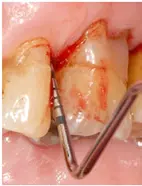

Man benötigt gerade in solchen Situationen ein ausreichendes Sortiment größerer Interdentalraumbürsten, wenn man das Ziel verfolgt, bei der Anwendung den jeweiligen Taschenfundus zuverlässig zu erreichen (Abb. 5).

Sowohl in der initialen Behandlungsphase nach Erstdiagnose einer Parodontitis als auch im Rahmen der Erhaltungstherapie (unterstützende Parodontitistherapie/UPT) besitzt die individuelle Mundhygieneschulung mit regelmäßiger Anpassung von Interdentalraumbürsten eine hohe Relevanz. Die Empfehlung der korrekten und passgenauen Interdentalraumbürste wird allerdings u. a. durch eine zu geringe Auswahl von Produkten mit größerer Reichweite erschwert.